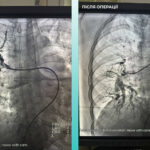

Медики выполнили тромбэктомию из мозговой и легочной артерий.

Одесситка попала в медучреждение с тяжелым острым мозговым инсультом, а во время обследования на компьютерном томографе врачи выявили закрытие средней мозговой артерии. Медики также зафиксировали, что пациентке тяжело дышать, поэтому дополнительно обследовали легкие и установили тромбоэмболию легочной артерии.

Мультидисциплинарная команда врачей приняла решение провести одновременную тромбэктомию из мозговой и легочной артерий. Операция прошла успешно, сейчас пациентка чувствует себя значительно лучше, она находится в сознании и уже двигает конечностями.